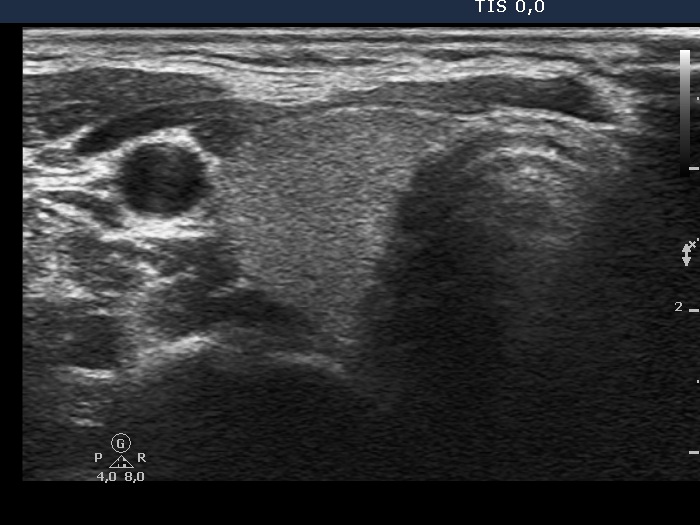

The role of complex diagnosis - not diagnostic cytology - Case 5. (ultrasonographic picture 1)

Lower pole of the right lobe, horizontal scan. There is a cystic nodule

.